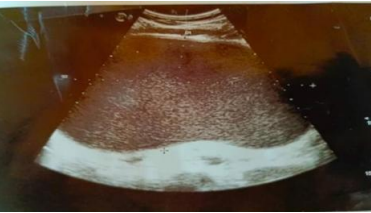

Abdominal Ultrasound: There is an epigastric simple cyst measuring 17x11cm with thickened wall measuring 5.8mm suggesting pancreatic pseudocyst.

Figure 4